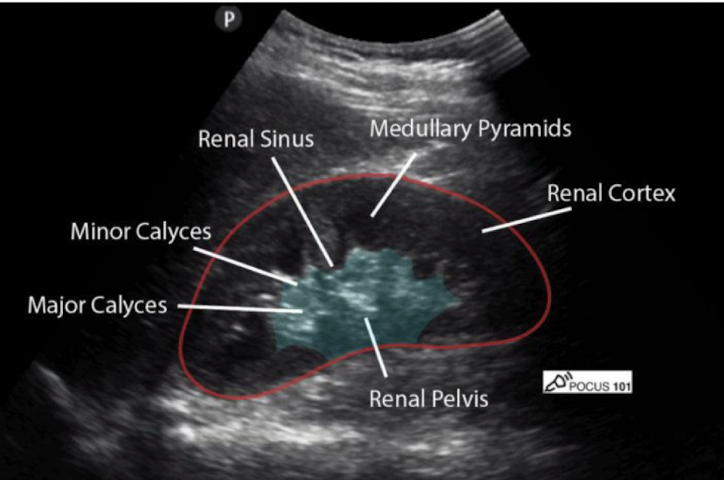

Review this image

What is the functional unit of the kidney?

Afferent arteriole → glomerulus → efferent arteriole → Bowmans capsule → proximal convoluted tubule → deceasing loop of henle → loop of henle → ascending loop of henle → distal convoluted tubule → collecting duct → minor papilla → minor calyx → major calyx → renal pelvis → ureter → bladder → urethra

papilla → minor calyx → major calyx → renal pelvis → ureter → bladder → urethra